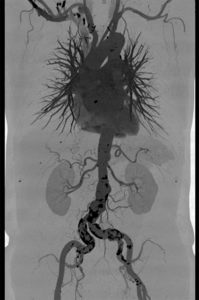

Für die Gefäßuntersuchung steht ein moderner 128-Zeilen-Computertomograf (Siemens Somatom Edge) zur Verfügung. Dieser kann bei einer räumlichen Auflösung von bis zu 0,3 mm kleinste Veränderungen nachweisen. Zur Darstellung der Gefäße wird dazu ein jodhaltiges Kontrastmittel verwendet, welches meist in eine Vene des Armes mit Hilfe einer Spritzenpumpe verabreicht wird. Die Untersuchung selbst dauert weniger als eine Minute.

Aus den dabei gewonnen Schnittbildern sind computergestützte 2D- und 3D-Rekonstruktionen aller Regionen des Gefäßsystemes herstellbar. Dieses Untersuchungsverfahren kommt in unserem Zentrum bei der Diagnostik – Erweiterungen der Bauchschlagader oder andere Gefäße, Durchblutungsstörungen aufgrund von Gefäßeinengungen oder Verschlüssen sowie der Therapieplanung und Therapiekontrolle – zum Einsatz. Einen wichtigen Stellenwert hat die Computertomografie auch bei allen akuten Gefäßerkrankungen und Gefäßverletzungen.